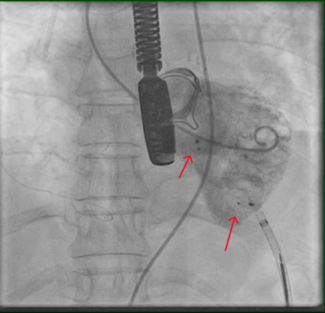

Case Report 1. A 63-year-old female patient with a past medical history significant for bilateral breast cancer status post bilateral mastectomies, chemotherapy, and radiation therapy presented with a 6-week history of slowly increasing swelling in her upper arms and neck. Her symptoms became suddenly worse 6 days prior to her ER visit and were associated with headaches and orthopnea. Prior to her admission, a chest CT scan with contrast was performed at an outside institution and was inconclusive. Given her clinical  presentation and the fact the she still had a venous port in her right subclavian vein, she was brought straight to the catheterization lab. Following informed consent and moderate sedation, an 8 Fr Pinnacle sheath (Terumo) was placed through the right femoral vein. A venogram of the SVC showed 100% occlusion (Figure 1). After infusion of 4000 international units of IV heparin, a 70 cm 8 Fr cook sheath (Cook Medical) was introduced. Using a Berenstein catheter (AngioDynamics) and a Glidewire

presentation and the fact the she still had a venous port in her right subclavian vein, she was brought straight to the catheterization lab. Following informed consent and moderate sedation, an 8 Fr Pinnacle sheath (Terumo) was placed through the right femoral vein. A venogram of the SVC showed 100% occlusion (Figure 1). After infusion of 4000 international units of IV heparin, a 70 cm 8 Fr cook sheath (Cook Medical) was introduced. Using a Berenstein catheter (AngioDynamics) and a Glidewire  (Terumo), the SVC occlusion was crossed and a venogram of the left internal jugular vein (LIJ) revealed a 100% stenosis of the distal LIJ and left subclavian system. An 8 Fr Trellis was then placed (Figure 2), isolating a 15 cm treatment zone between the SVC and the LIJ. We delivered 10 mg of t-PA over 12 minutes with complete removal of the thrombus. Another venogram of the SVC showed a right innominate vein thrombus. Using a Berenstein catheter (AngioDynamics), we then crossed with an exchange-length Wholey wire (Mallinckrodt) to the right internal jugular vein (RIJ). An 8 Fr Trellis with a 15 cm treatment zone was advanced into the right subclavian vein (RSV) and 10 mg of t-PA were delivered between the SVC and the RSV over a 10-minute period. Following thrombus aspiration, scar around the port just distal to the SVC was noted and was dilated with 10 mm x 40 mm and 12 mm x 40 mm Agiltrac balloons (Abbott Vascular), with excellent results (Figure 3). Patient’s symptoms improved substantially during her hospital stay and she remained asymptomatic at her 6 months post-procedural follow-up visit.